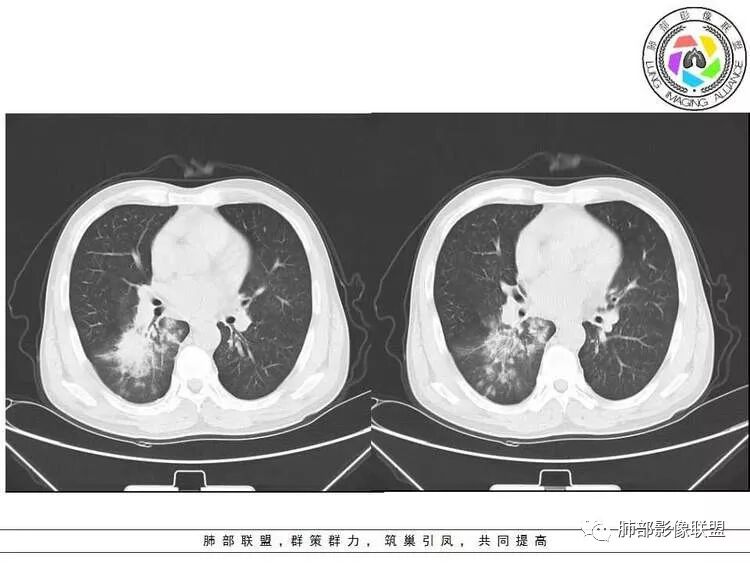

南边:紧贴着斜裂过来的一个病灶,它的特点是:外围大,内带小。它整个下叶背段体积与对侧相比稍微缩小一点,但是缩小地不是很厉害。外支朝前下走了,仔细看血管,肺动脉走行自然,直达远端。远端实变区是肉芽肿成分,稍微有一点低密度,没有明显坏死,稍微有一点点坏死。而且附近有很多卫星灶,附近很多斑片影,有一些明显有气道壁增厚,细支气管炎的特点,还有就是下叶其他段很多斑片状影。换个角度,第一如果是肺癌,刚才看到PET-CT提示肺癌伴阻塞性肺炎,这个是不符合的。第二如果是肺癌阻塞性肺炎,近端血管肺动脉走行不会那么自然集聚的,这个是不符合的。理由是:如果这个病灶是肺癌,那么明显属于中央型肺癌,中央型肺癌的特点是近端大,远端小,近端是一个肿块,远端阻塞,远端阻塞是阻塞性炎症或者不张,它应该体积缩小,斑片状实变,不会这么密实。刚才有老师提到支气管,这个片有缺陷的地方,给的图像好像那层,如果把其他图像拿开再重叠一下。

如果是单纯看这幅图像,会觉得背段外侧支气管分支堵塞的,但是看下面这层图

南边:你就发现外侧支气管朝下走的分支非常自然,通畅的。